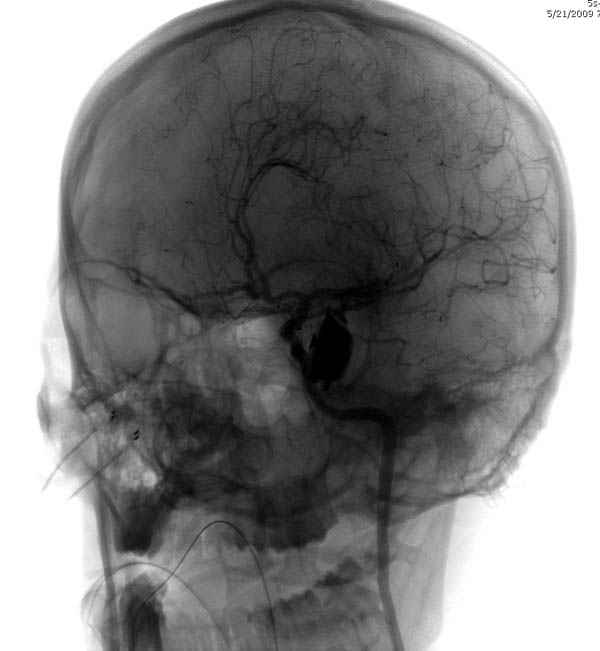

В своих выступлениях я рассказывал, что наши центры в мирное время по пенетрирующим травмам не уступает Ираку или Афганстану, и вот недавно к нам поступила больная 22 лет, травма "ножом в глаз" от бывшей подруги нынешнего "бой френда".

При поступлении в сознании, жаловалась на неприятные ощущения в глазнице.

По протоколу сделаны все необходимые исследования: рентген, ангиограмма с 3Д реконструкцией, где обнаружили что все жизненно важные сосуды не задеты, даже некоторые "сидят" изгибаясь на ноже.

Одним махом нож удалить не удалось, пришлось раскачать и потом двумя руками удалили нож. Рана без кровотечения, обработана и зашита.